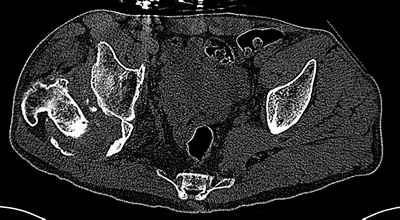

Пациент 30 лет 3 года назад в результате травмы получил травматический

дефект нижних конечностей до в/3 голеней, был пропущен вывих бедра. В настоящее время очень

неплохо ходит на протезах, движения в неоартрозе близки по объему к здоровой стороне.

Основная жалоба - выраженная боль при ходьбе. планируем двухэтапное эндопротезирование -

задним доступом мобилизовать проксимальный отдел бедра, резецировать шейку, аппаратом

низвести бедро(головку оставить там где она есть, так как больших дефектов не видно(может

пригодится в последующем?)). Вторым этапом бесцементное эндопротезирование. Насколько

такой вариант реалистичен? Доступ для второго этапа? Может быть, другие варианты?